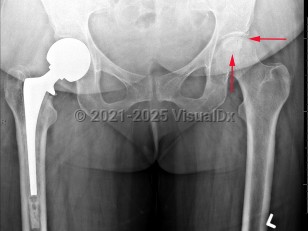

Grade / classification system: The Ficat classification system is based on plain x-rays and the patient's symptoms.

- Stage 0: normal x-rays, asymptomatic; "silent hip" if patient has known contralateral AVN

- Stage I: normal x-rays or subtle trabecular blurring or osteopenia; pain and limited hip range of motion

- Stage II: normal contour of the femoral head but with cystic or sclerotic evidence of bone remodeling; worsening clinical signs

- Stage III: "crescent sign," abnormal contour or flattening of the femoral head from subchondral collapse with joint space preserved

- Stage IV: degenerative osteoarthritis with narrowed joint space and osteophytes; progressively diminished hip motion